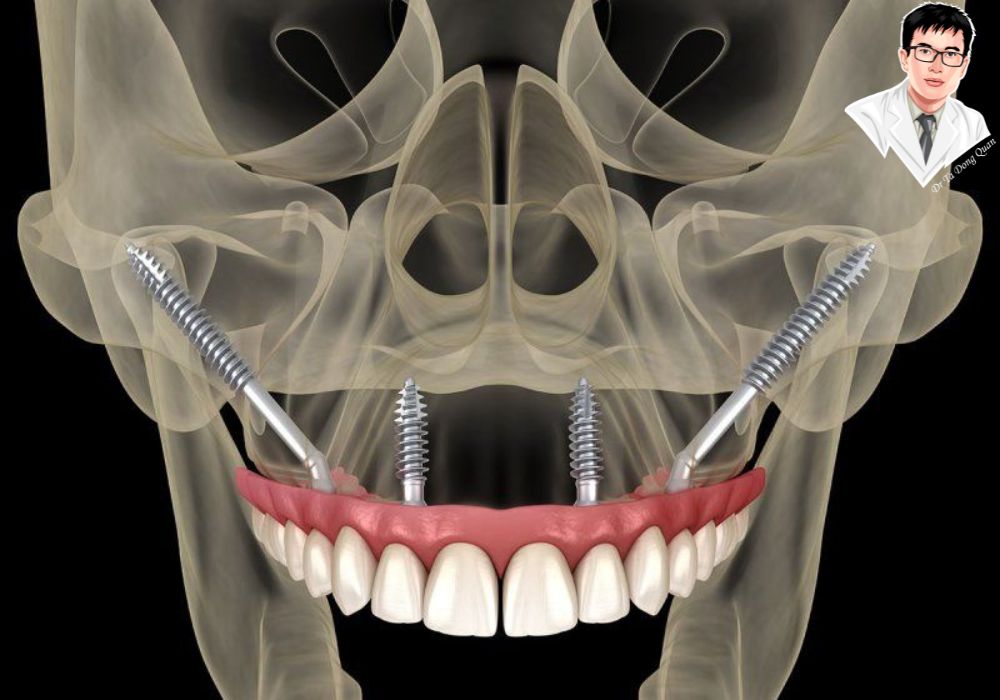

Hình ảnh 3D mô phỏng vị trí cấy ghép implant Zygoma ở hàm trên, cho thấy cấu trúc bám vào xương gò má.